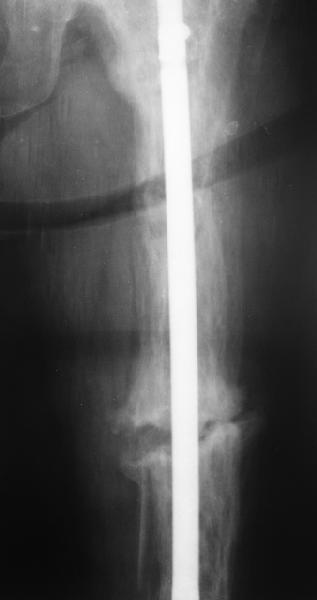

Re: перелом бедра на фоне болезни Педжета

Еще один пример. Пациентка с юга России, прислала рентгенограммы через год. На сегодня прошло 2 г. 8 мес. после операции. Несмотря на не очень убедительный процесс сращения, пациентка ходит. Учитывая остеопороз при Педжете, решили, что динамизировать вообще не нужно.